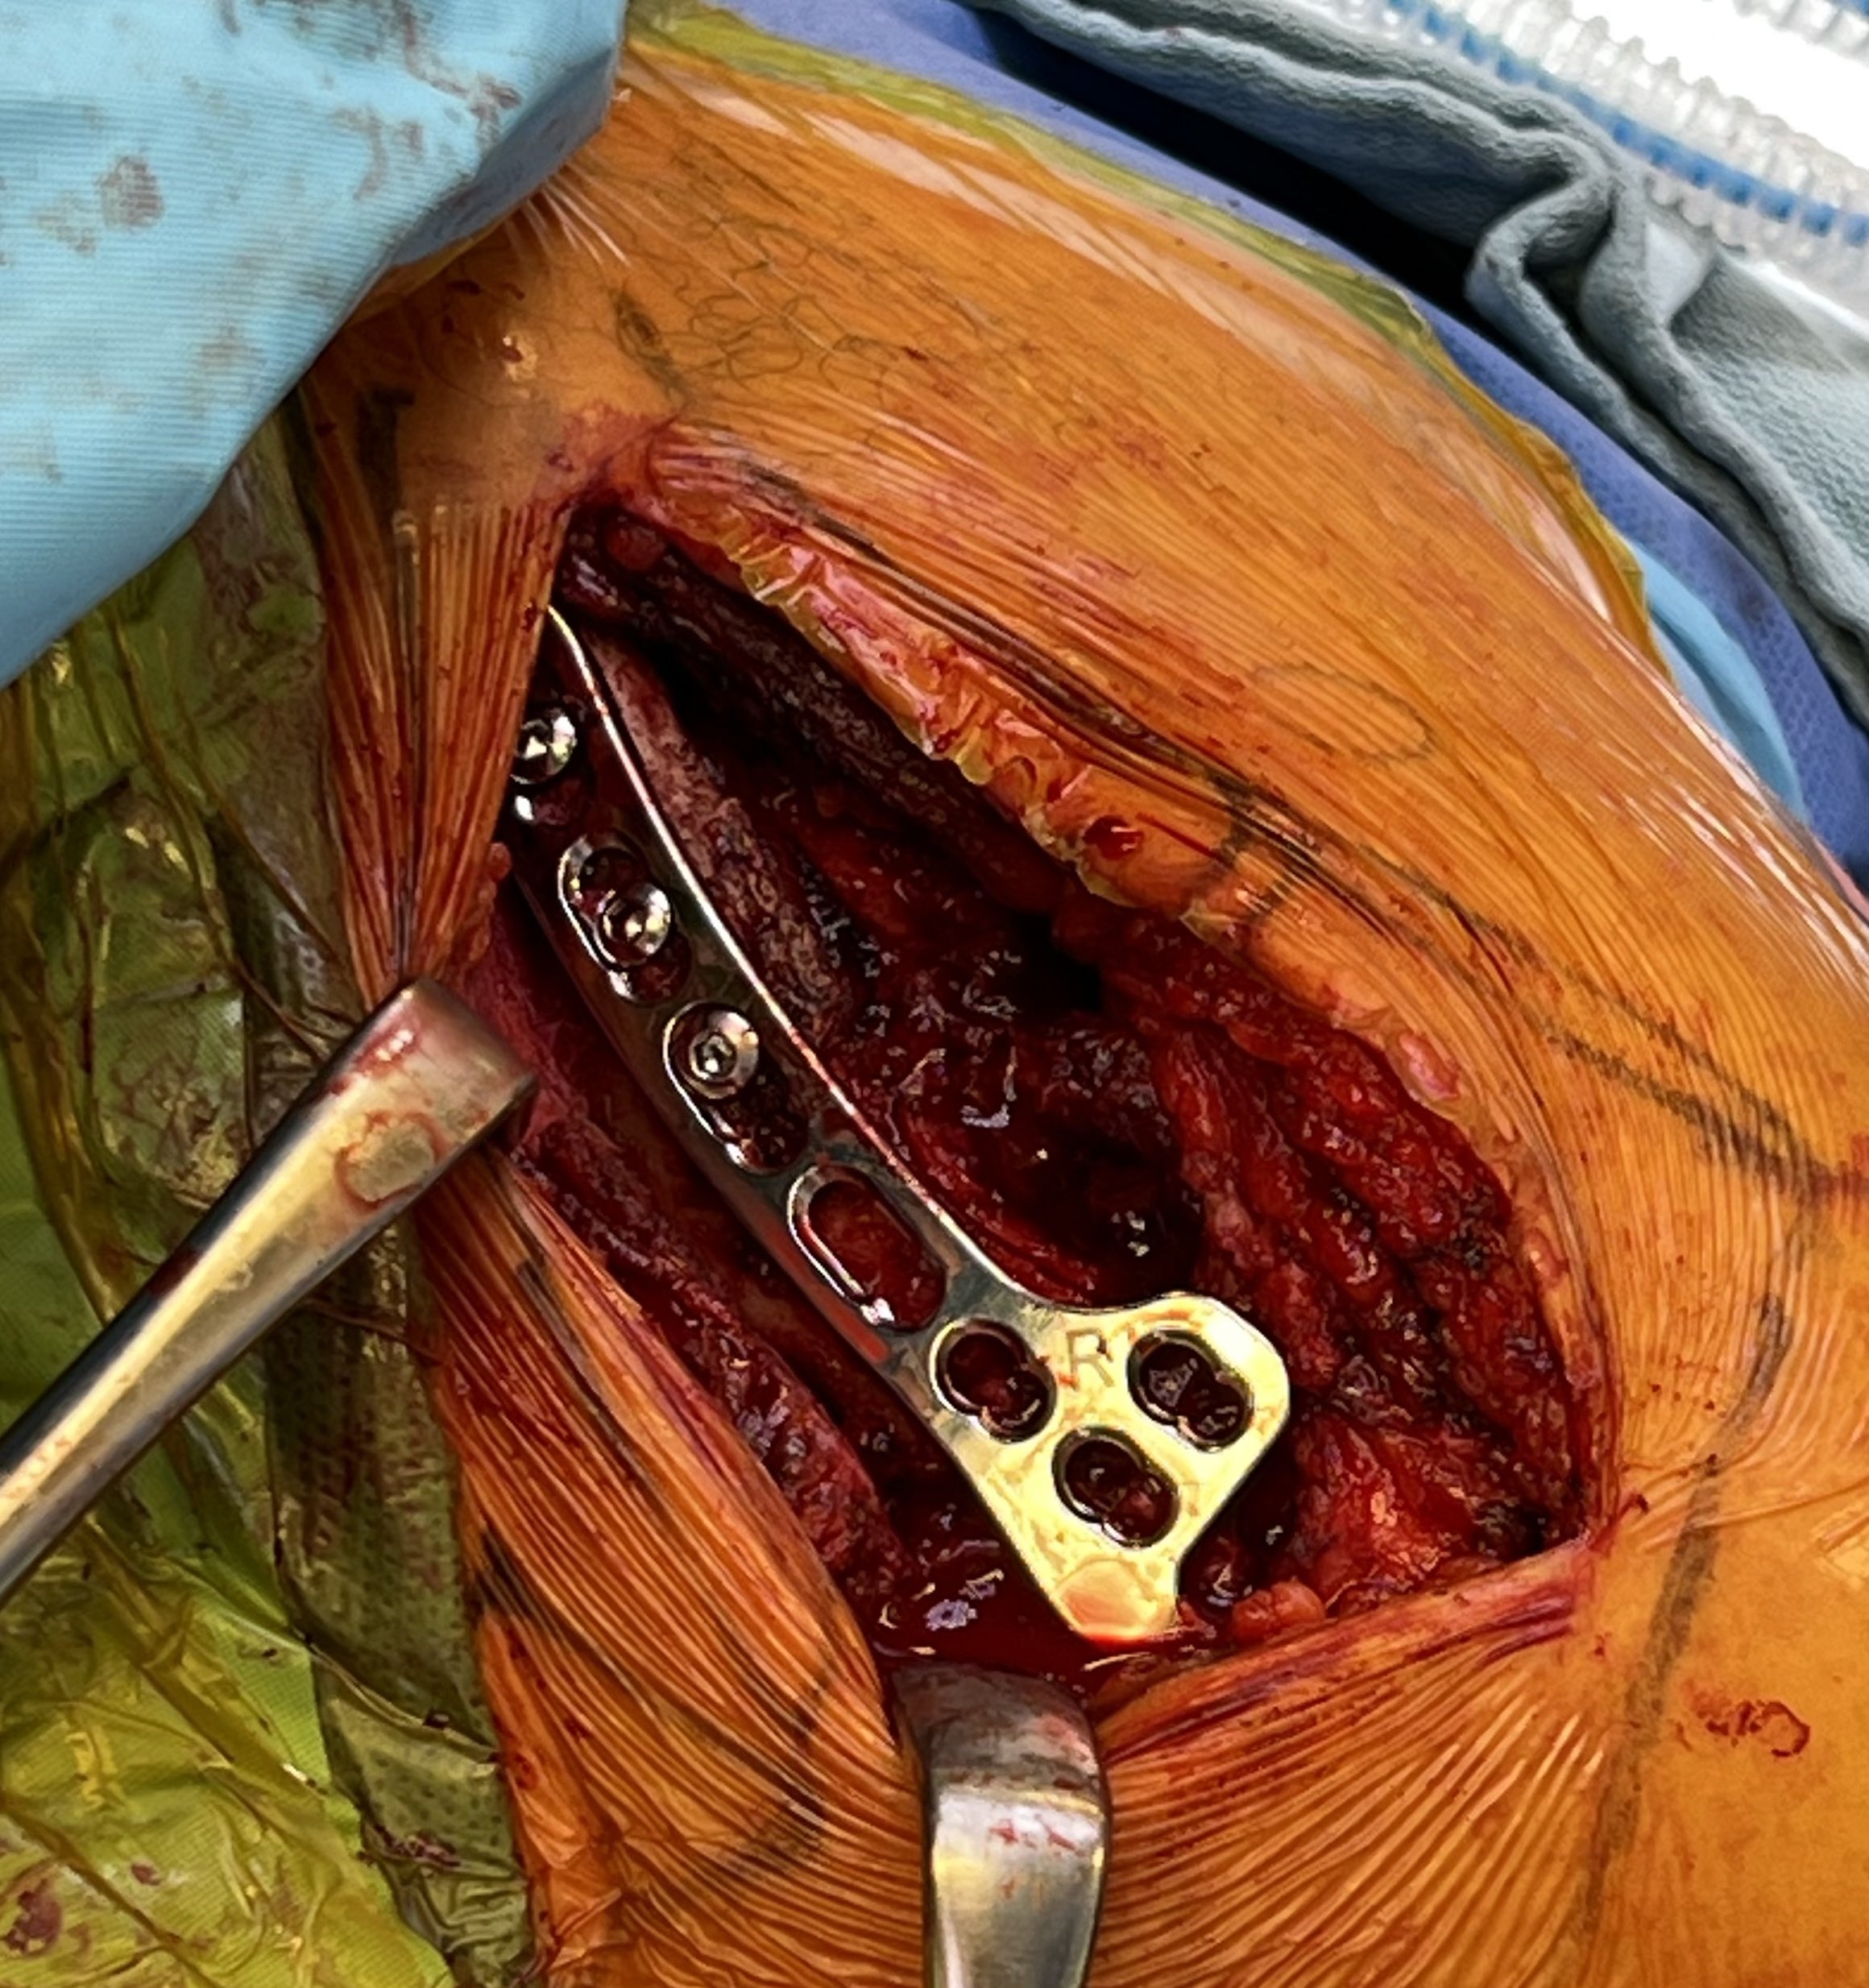

Technique

Dorsal locking plate with cerclage fibretape

Lazy beach chair

- divide deltoid-trapezius fascia

- expose clavicle

- clean and reduce fracture

- plate fracture

- expose coracoid

- suture anchor / suspensory fixation / cerclage tape or graft